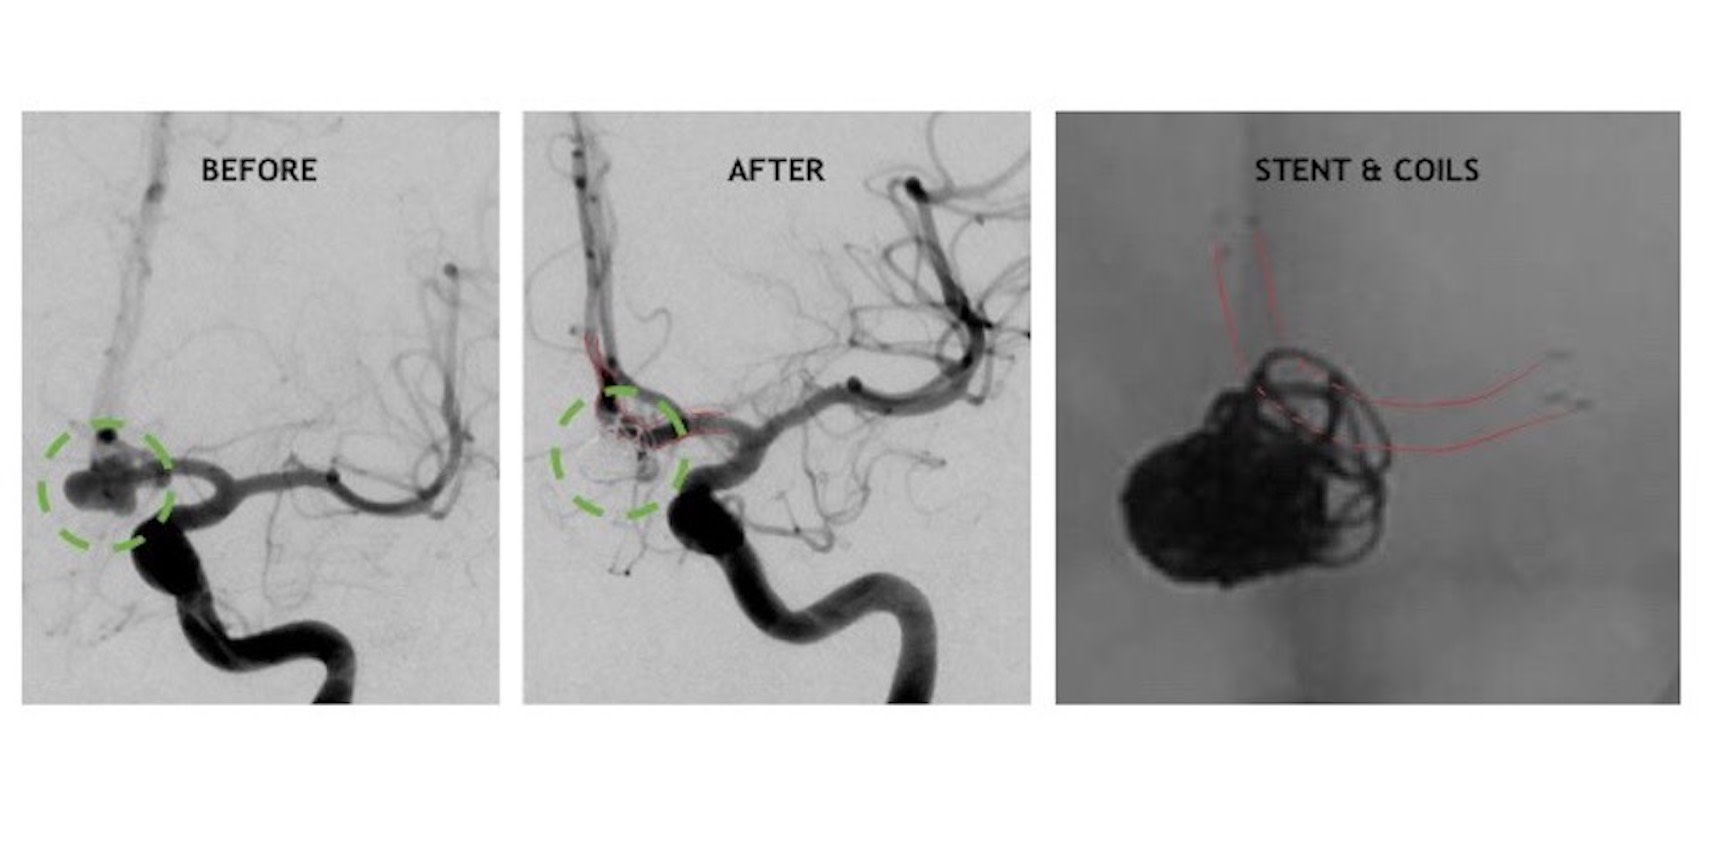

From www.ahajournals.org

StentAssisted Coil Embolization of a Large Fusiform Aneurysm of Coiling Coronary Aneurysm The vast majority of coronary artery aneurysm and coronary artery ectasia is detected incidentally during coronary angiography or computed tomography. Treatment options include medical management, surgical excision, coronary bypass grafting (cabg), and percutaneous coronary. This procedure is also called endovascular embolization. Coronary artery aneurysms (caas) are uncommon and describe a localized dilatation of a coronary artery segment more than 1.5.. Coiling Coronary Aneurysm.